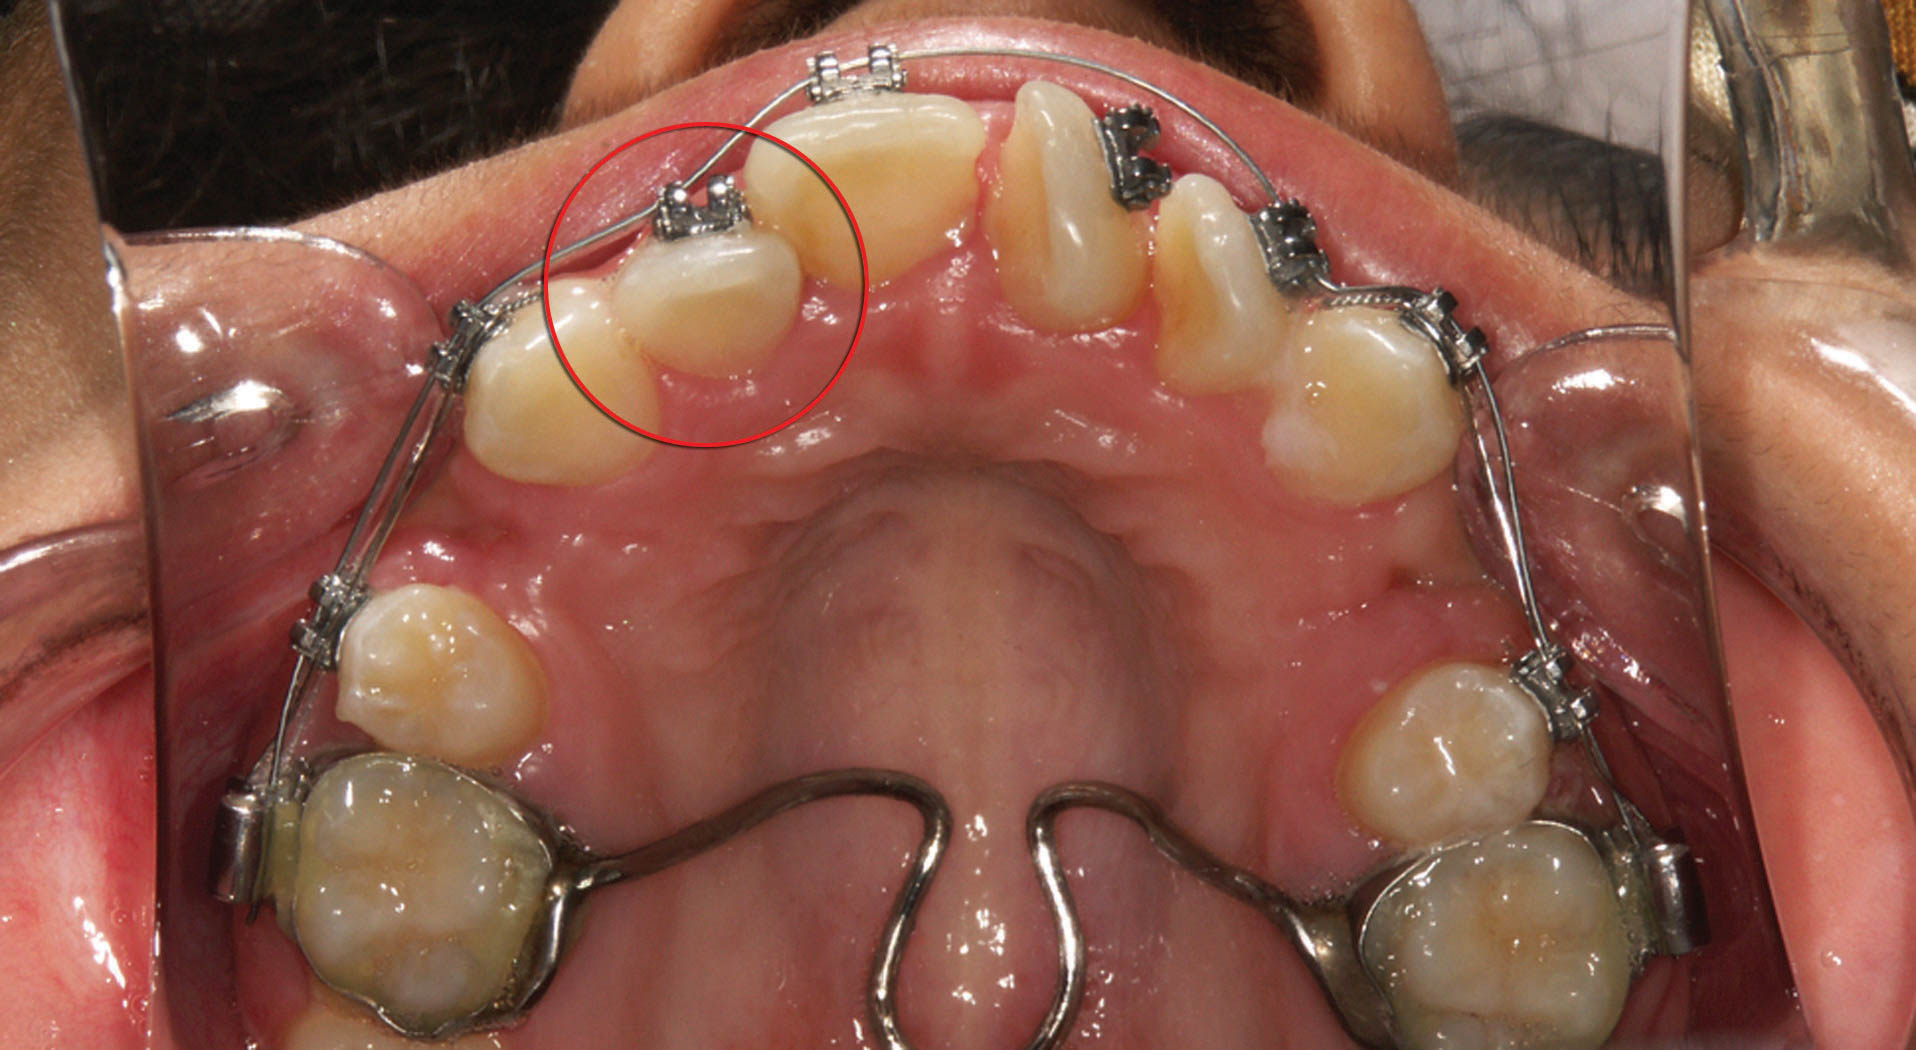

4. دندان 4 بالا که بجای 3 قرار میگیرد: اگر کانین کشیده شده (شکل 88-1) یا missing لترال دارید و کانین را بجای لترال قرار دادهاید (شکل 89-1) براکت 4 را 0.5mm دیستالیتر بچسبانید تا دیستال آن باکالیتر شود و حالت برجستگی کانینی ایجاد نماید.

ترتیب دندانها در انتهای درمان این بیماران به صورت سانترال، کانین و پرمولر میشود. با نگاه به لثه آنها میبینید که مارجین لثه ارتفاع خوبی ندارد. چون همیشه لترال بین سانترال و کانین است و لثه آن ارتفاع پایینی دارد در حالی که در این بیماران کانین بین سانترال و پرمولر قرار گرفته و مارجین آن بالاتر و مارجین پرمولر پایینتر است بهتر است در این گونه بیماران برای زیبایی بیشتر لثه، براکت کانین را 1mm ژنژیوالیتر و پرمولر اول را 1mm انسیزالیتر بچسبانید تا با اکسترود و اینترود نسبی این دندانها لثه زیباتر به نظر بیاید. در انتهای درمان حتماً با کارهای ترمیمی فرم تاج را زیباتر کنید.

شکل 89-1: فقدان دندان لترال، لذا کانین به جای لترال قرار گرفته و پرمولر اول حکم کانین را دارد.